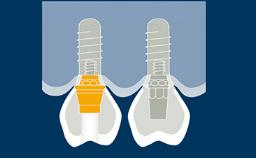

Independentemente da localização ou extensão do tratamento, o planejamento da terapia com implantes deve ser sempre orientado pela prótese. Isso garante que a instalação do implante atenderá às necessidades protéticas e será compatível com o resultado final desejado. Com o objetivo de alcançar um resultado ideal, o planejamento protético deve considerar todos os fatores protéticos relevantes e um modelo diagnóstico adequado como base para o planejamento específico das próteses sobre implante e implantes de suporte.

- delinear os pontos de planejamento específicos para próteses sobre implante e seus implantes de suporte